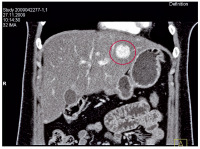

CT des Oberbauchs mit Kontrastmittel

Abbildung 2: CT des Oberbauchs mit Kontrastmittel: In der portalvenösen Phase homogene Kontrastmittelanfärbung eines Pelioseherdes im Lebersegment 2. Ein weiterer, kleiner, homogen angefärbter Herd zeigt sich am Unterrand der Leber.

Keywords: CThomogene KontrastmittelanfärbungKontrastmittelLebersegment 2OberbauchPelioseherdportalvenöse Phase

Abbildung 3: CT des Oberbauchs mit Kontrastmittel: In der portalvenösen Phase homogene Kontrastmittelanfärbung eines Pelioseherdes im Lebersegment 4b.

Keywords: CThomogene KontrastmittelfärbungKontrastmittelLebersegment 4bOberbauchPelioseherdportalvenöse Phase